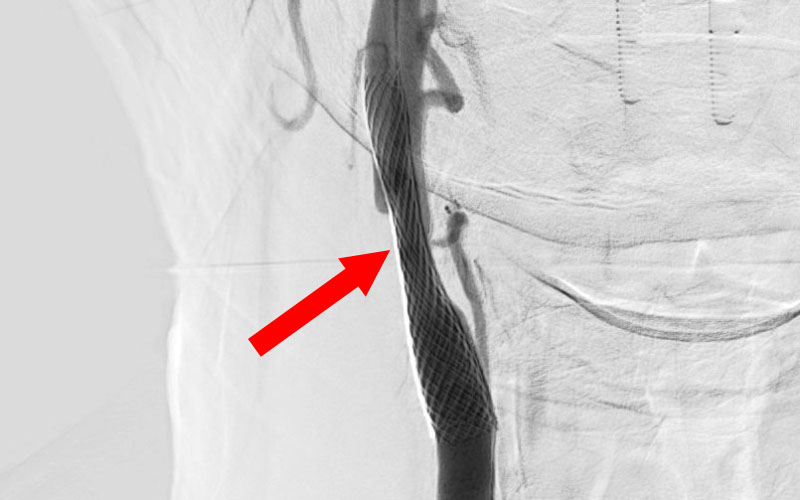

右頚部内頚動脈狭窄症

80代

院内外来

No.1490 手術前

No.1490 手術中

No.1490 手術後